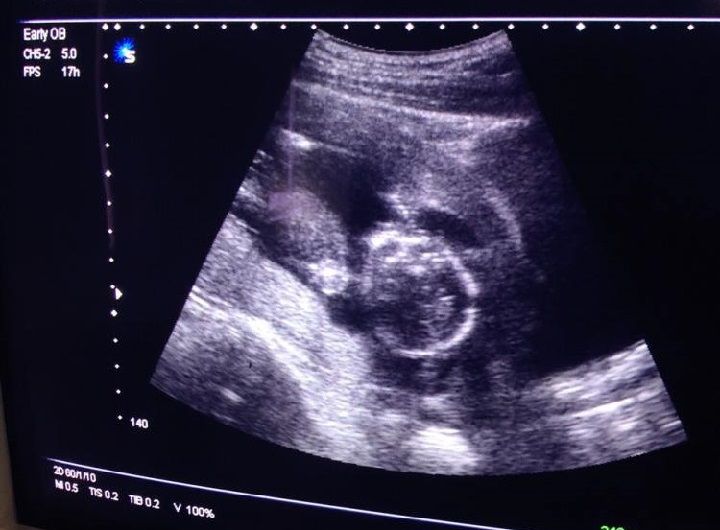

第一、超声检查失误

孕妇怀孕四到五个月的时候,宝宝的生殖器官已经发育到一定程度,基本上都可以判断出宝宝的性别。对于男宝宝来说生殖器官很好辨认,但是对于女宝宝来说就不是那么明显了,由于在检查的过程中,受到多方因素的影响就会出现检查结果不准确的现象。

第三、孕妈肚子里的胎儿不配合

在做检查的时候,胎儿的体位非常关键,如果在检查的时候刚好赶上胎儿不配合,那么也没有办法。很有可能胎儿把非常关键的部位遮挡住了,这时候检查结果就会出现失误。在正常情况下,如果医生的水平较高,而且宝宝的体位也属于正常,都可以看清宝宝的性别。